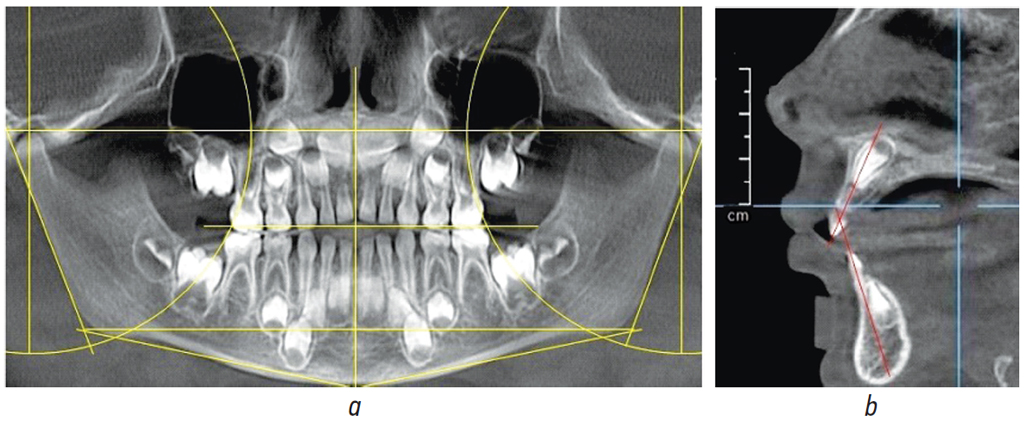

Средняя величина вертикальной резцовой дизокклюзии во всех вариантах составляла 4,87 ± 1,22 мм. Наиболее частым вариантом резцовой дизокклюзии была сочетанная форма, при этом отмечалось увеличение межрезцового угла на боковой томограмме (рис. 2).

Рис. 2. Анализ расположение ориентиров на ортопантомограмме (а) и томограмме (b)

Fig. 2. Analysis of the location of landmarks on the orthopantomogram (a) and tomogram (b)

При данной форме верхние резцы располагались выше окклюзионной линии, а нижние резцы не доходили до указанной горизонтали. Как правило, все три горизонтали располагались параллельно друг другу, что характеризовало зубоальвеолярную форму патологии. Величина угла нижней челюсти составляла 123,29° ± 2,87°, что близко к оптимальной физиологической норме. Обращает на себя внимание положение суставной окружности, которая проходила по дистальной окклюзионной точке с обеих сторон и свидетельствовала об оптимальном расположении вторых молочных моляров. Срединная вертикаль лица проходила между медиальными резцами обеих челюстей, что характерно для симметричных форм зубочелюстных дуг.

На 3D-томограммах детей исследуемой группы величина лицевого угла по Шварцу в среднем составляла 85,12° ± 1,09° и была характерна для оптимального расположения верхней челюсти в структуре краниофациального комплекса. Угол A-N-B был равен 2,87° ± 1,02°. Величина нижнечелюстного угла 3D-томограммы практически соответствовала данным ортопантомограммы. Величина гнатического угла отличалась от расчетных показателей в среднем на 3,62° ± 1,12°, что свидетельствовало об увеличении высоты гнатического отдела по сравнению с назальным отделом лица (рис. 3).